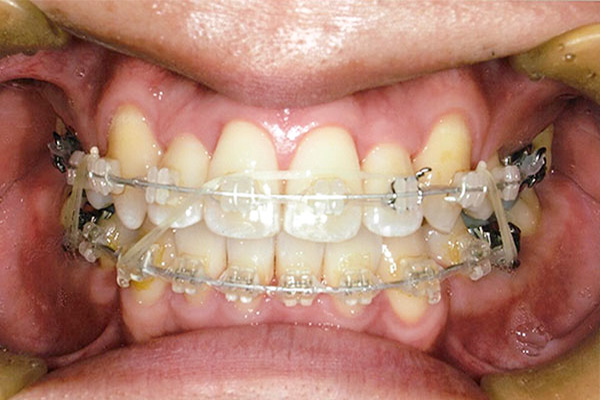

1年後